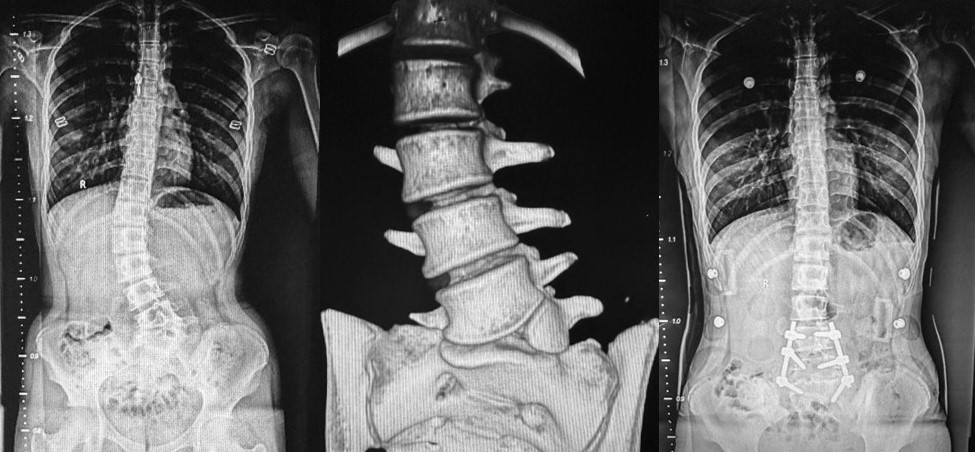

病例1是一名14岁青少年,诊断为腰骶部半椎体畸形,自两年前被确诊后一直佩戴支具治疗,但效果不佳,随着时间推移,体态变形日益明显,脊柱侧凸逐渐加重,感觉双腿一长一短,日常工作和生活受到极大影响。科主任王栋教授组织全科讨论评估患者病情,做了详细的术前评估,并制定了完善的手术方案。由王栋主任、蔡璇副主任及王瑞主治医师为患者实施了经后路腰骶段半椎体切除椎弓根螺钉内固定植骨融合术,手术过程顺利,取得满意的矫形效果,助力患者挺起脊梁(图1)。

病例1:腰骶部半椎体畸形,行半椎体切除短节段固定融合术